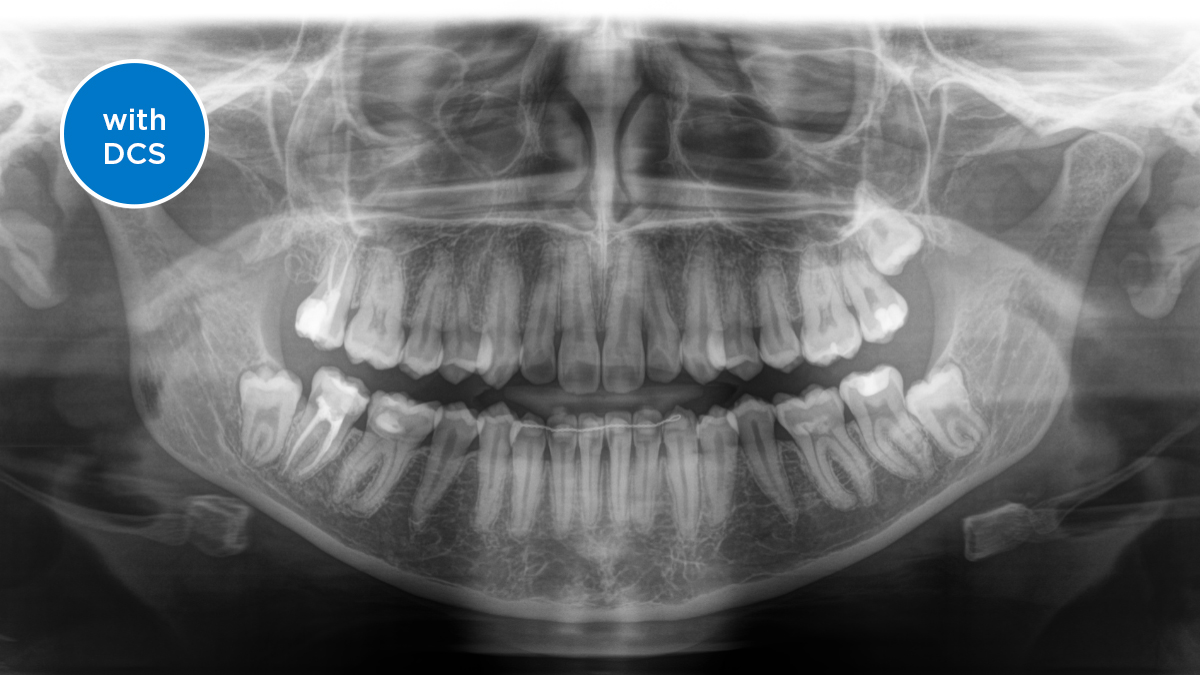

The Direct Conversion Sensor (DCS) has revolutionised the standard of panoramic imaging. X-rays are converted directly into electrical signals. Thus, there is no signal loss due to light conversion, as is the case with conventional systems. The result: images with a high level of sharpness and contrast – even at an extremely low radiation dose. For accurate diagnostic information to support targeted treatment.

The image below shows a panoramic X-ray without and with DCS technology. Using the arrow, drag the control across the image to see the difference the direct conversion sensor makes to the image quality and diagnostic possibilities.